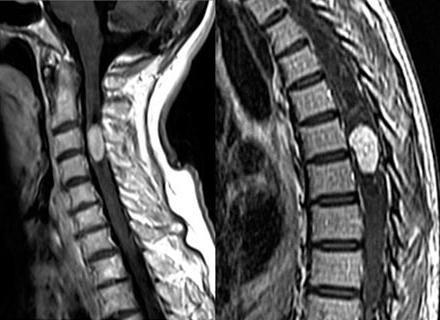

- Ressonância Magnética (RM):

- Padrão ouro para avaliação detalhada de tecidos moles e estruturas da coluna.

RMN DE COLUNA CERVICAL E TORÁCICA: TUMOR INTRAMEDULAR